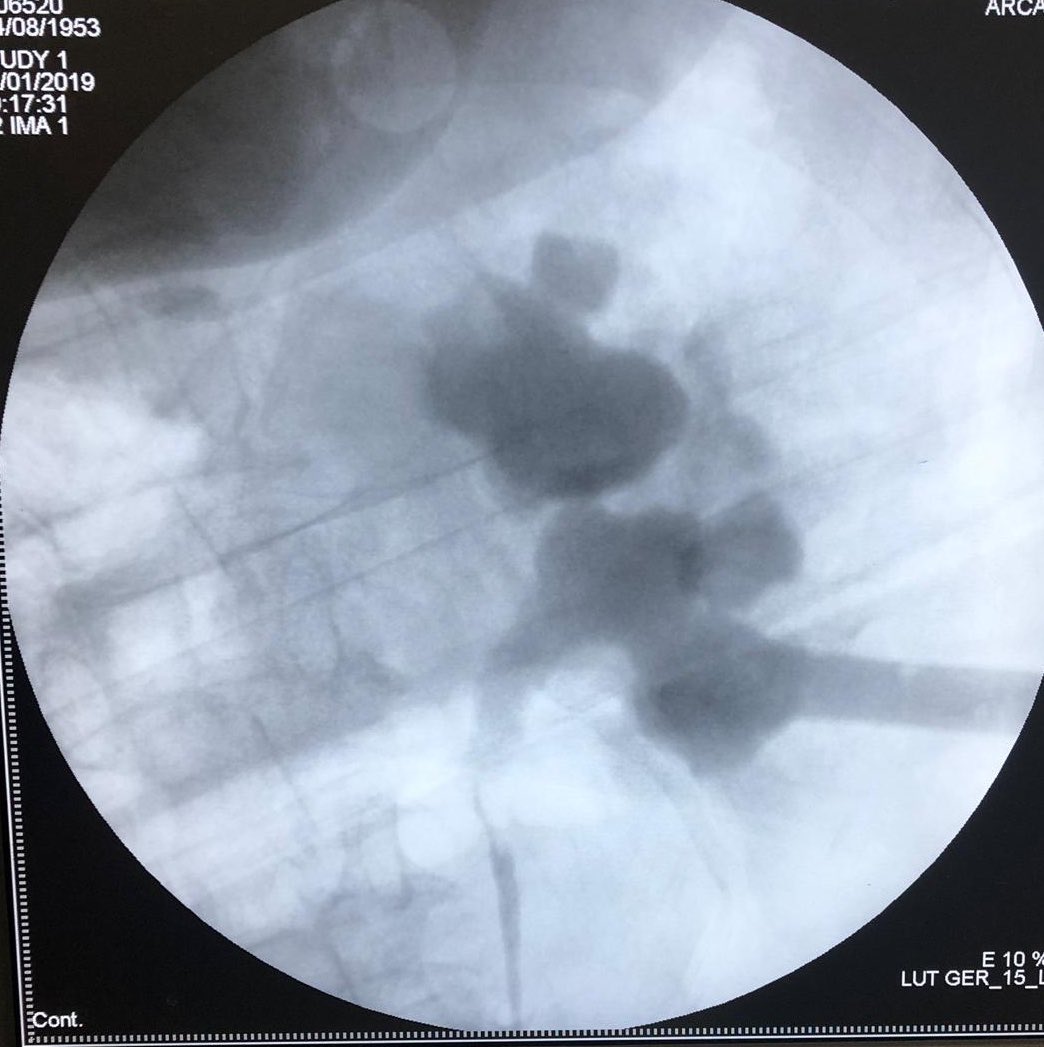

Open anatrophic nephrolithotomy is not a #Cure is to prolong & complicate the suffering of our patients. It results in: an abnormal anatomy with subsequent infections, recurrent stones & lost renal ftn. Better #PCNL & do not damage patients.

Today with our fellows, we performed #USG percutaneous puncture 4 a standard #PCNL (26F) with #Alken dilatation. On my personal experience safety to patients is our primary goal & stone free & dilation needs X-Ray control. @emiliani_e @ytanidir @Urologeman @natxo73 @cmordin75